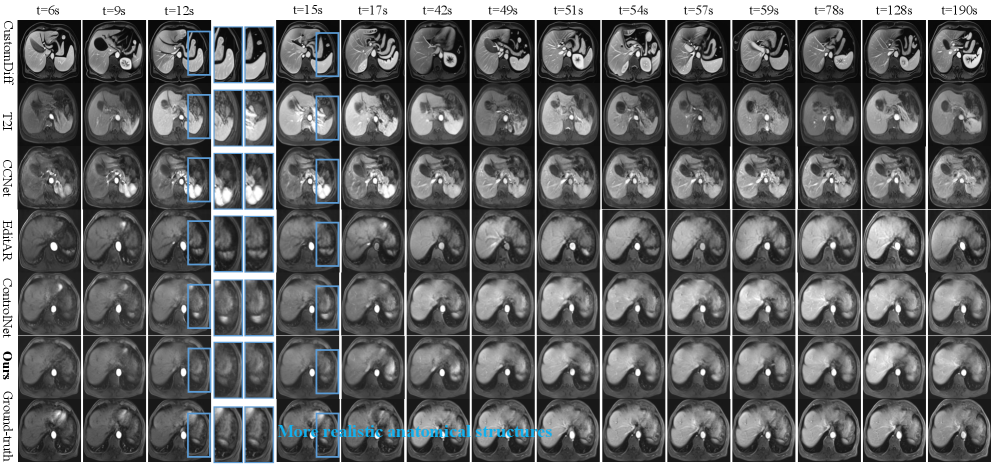

Refer to caption

Figure 4: Visualization results in Abdominal DCE-MRI: The visualization results of our methods on different time points exhibit better spatial reality (zoom-in regions in blue boxes) and temporal continuities than comparisons (connected green boxes), whereas other methods show deviations from realistic kinetics or lack of dynamic consistency.

Visualization Results Analysis As shown in Fig.4 and Fig.5, the visualization sequences of both datasets demonstrate that our method achieves high spatial reality and natural kinetics, both closely matching the ground-truth. CustomDiff and T2I generated images with severe deviations from the ground-truth, suffering from blurred organ contours and distorted dynamic enhancement gradients of contrast agents. CCNet failed to converge, leading to excessively smooth images, severe spatial structural distortion, and the appearance of color blocks, which is consistent with the previously analyzed characteristic of high PSNR. EditAR and ControlNet have normal spatial structures, but their kinetics both deviate from the normal pattern. More visualization results are in Supplementary.

Figure 9: Visualization results of spleen in Abdominal DCE-MRI shows that our CEKWorld conforms to the spleen contrast agent kinetics, exhibiting the characteristics of rapid synchronous enhancement, progressive homogenization, and sustained homogeneous high signal. In contrast, methods such as ControlNet and CCNet have defects, including delayed start of enhancement, abnormal intensity, or content distortion.

Figure 10: Visualization results of liver in Abdominal DCE-MRI shows that our CEKWorld conforms to the contrast agent kinetic laws of hepatic vessel progressive enhancement and liver parenchyma’s regular enhancement-washout. In contrast, other methods exhibit distorted contents, while ControlNet suffers from non-physiological hepatic vessel enhancement delay, confirming our spatiotemporal consistency learning accurately captures liver contrast agent kinetics.

Figure 11: Visualization results of kidney in Abdominal DCE-MRI shows that our CEKWorld reproduces the typical renal perfusion pattern of cortical edge enhancement first, gradual diffusion to the medulla until homogeneity, while methods such as T2I and CCNet have problems of abnormal enhancement or blurred structure, and ControlNet lacks dynamics in the delay phase.

Figure 12: Visualization results in Abdominal DCE-MRI: The visualization results of our methods on different time points exhibit better spatial reality (zoom-in regions in blue boxes).

Spleen As shown in Fig.9, CEKWorld conforms to the contrast agent kinetics of the spleen at all time points [47, 12, 77, 87]. In the early arterial phase, when t=6s and 9s, CEKWorld initiates enhancement rapidly and synchronously with the ground-truth, showing typical patchy heterogeneous hyperintensity. In contrast, ControlNet has an obvious delay with slow initiation of enhancement, and methods such as CCNet exhibit abnormal enhancement intensity. In the middle arterial phase, when t=12s and 15s, the enhancement of CEKWorld gradually transitions from patchy to homogeneous, which is completely consistent with the physiological process of contrast agent gradual diffusion in the splenic red pulp sinuses. In contrast, other methods either have distorted enhancement morphology or disordered rhythm. In the late arterial phase and vein phase, when t=17s and 42s, CEKWorld continuously maintains homogeneous hyperintensity without abnormal washout, perfectly matching the imaging feature of the spleen that enhancement lasts long and becomes homogeneous in the later stage. However, other methods have already shown signal distortion or abrupt transition.

Liver In Fig. 10, we visualize the predicted dynamic contrast enhancement of the liver across multiple time points. CustomDiff, T2I, CCNet and EditAR all struggle to reproduce realistic liver kinetics [76, 6]: vascular structures either fail to enhance at the appropriate phases or exhibit unstable parenchymal signals, with noticeable frame-to-frame fluctuations and over-smoothed textures. ControlNet shows better anatomical fidelity but presents a clear liver vascular enhancement delay—hepatic vessels remain under-enhanced in the early arterial and early portal phases and then suddenly become hyperintense several frames later, resulting in a phase-shifted and non-physiological enhancement pattern. In contrast, our method closely follows the ground truth: the hepatic vessels in the green ROI show progressive enhancement, with smooth, timely transition from arterial to portal venous and delayed phases, while the liver parenchyma brightens and washes out in a gradual, temporally coherent manner. This demonstrates that our spatiotemporal consistency learning not only preserves realistic liver anatomy but also captures the correct contrast-agent kinetics over time.

Kidney In Fig.11, the contrast agent kinetics in the renal cortex–medulla region highlight that our CEKWorld shows more similarities with the ground-truth sequence. In the ground-truth sequence, enhancement first appears along the cortical rim on the edge, gradually propagates toward the medulla in the center, and finally becomes spatially homogeneous at late phases, exhibiting a typical outside-in renal perfusion pattern [60, 11]. T2I and CCNet either under-enhance or severely corrupt textures, making the cortical–medullary layers indistinguishable; EditAR shows weak and unstable enhancement; and ControlNet suffers from a lack of smooth temporal evolution. In contrast, our CEKWorld reproduces early cortical enhancement, its gradual inward spread, and the final homogeneous enhancement in a structurally faithful and temporally continuous manner, yielding renal contrast dynamics that best match real DCE-MRI.

7.2.2 Visualization of Spatial Structures in Abdominal DCE-MRI

In Fig.12, our methods exhibit better anatomical fidelity. CCNet introduces strong, grainy noise and artifacts in the spleen and liver parenchyma, tearing and blurring organ boundaries, and severely distorting the underlying anatomy. EditAR preserves a roughly correct global outline, but local details fluctuate strongly between neighboring frames: the splenic hilum and adjacent parenchyma alternately swell and collapse, yielding unstable textures. ControlNet largely retains coarse organ shape, yet its internal structures gradually blur, and vessel–parenchyma interfaces drift slightly, indicating mild geometric shift and loss of structural sharpness. In contrast, our MRI CEKWorld consistently preserves spleen contours, liver parenchymal shape, and vascular trajectories that closely match the ground truth. The blue-highlighted regions reveal that our results are the closest to the reference in both organ geometry and texture distribution, demonstrating the effectiveness of our spatial regularization in enforcing patient-specific anatomical consistency.